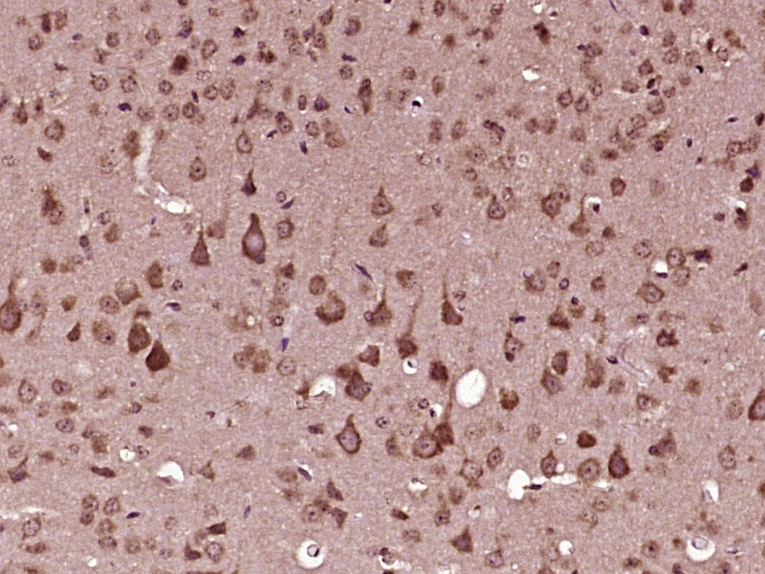

Paraformaldehyde-fixed, paraffin embedded (mouse brain tissue); Antigen retrieval by boiling in sodium citrate buffer (pH6.0) for 15min; Block endogenous peroxidase by 3% hydrogen peroxide for 20 minutes; Blocking buffer (normal goat serum) at 37°C for 30min; Antibody incubation with (RAPGEFL1) Polyclonal Antibody, Unconjugated (bs-21157R) at 1:400 overnight at 4°C, followed by operating according to SP Kit(Rabbit) (sp-0023) instructionsand DAB staining.